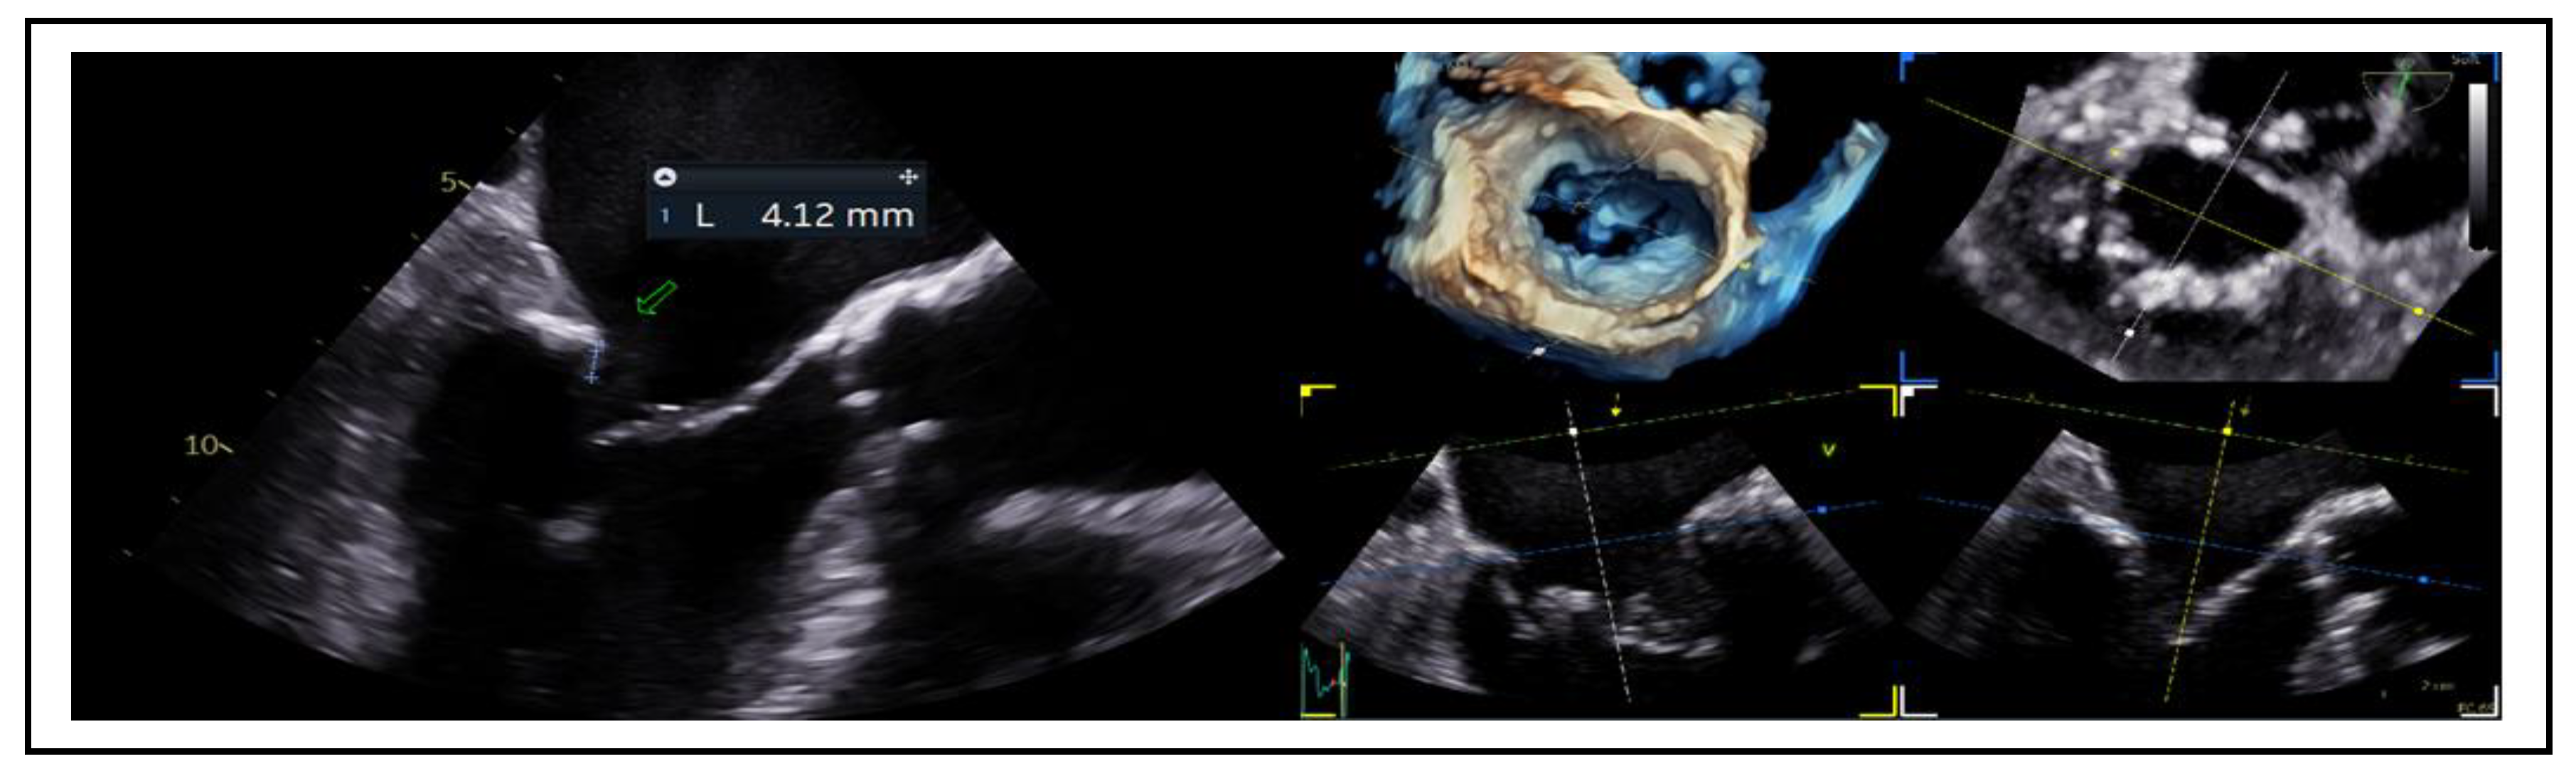

7.2. Posterior Leaflet Length

7.3. Mitral Valve Area and Gradient